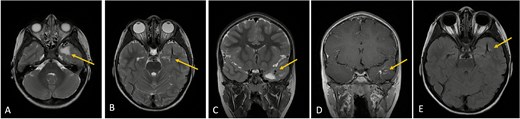

Clinical and radiological follow-up was advised. Serial MRIs at two and four months demonstrated no change in venous morphology or white matter signal. The patient’s clinical course remained uneventful, with no neurological deficits noted (Fig. 3).

Axial lower cut (A)/axial higher cut (B)/coronal (C) T2-weighted MRI of the brain shows stable findings of a prominent area of T2 hyperintensity in the white matter of the left anterior temporal lobe, adjacent to the known DVA (arrow), which is clearly delineated on the contrasted sequence (D).